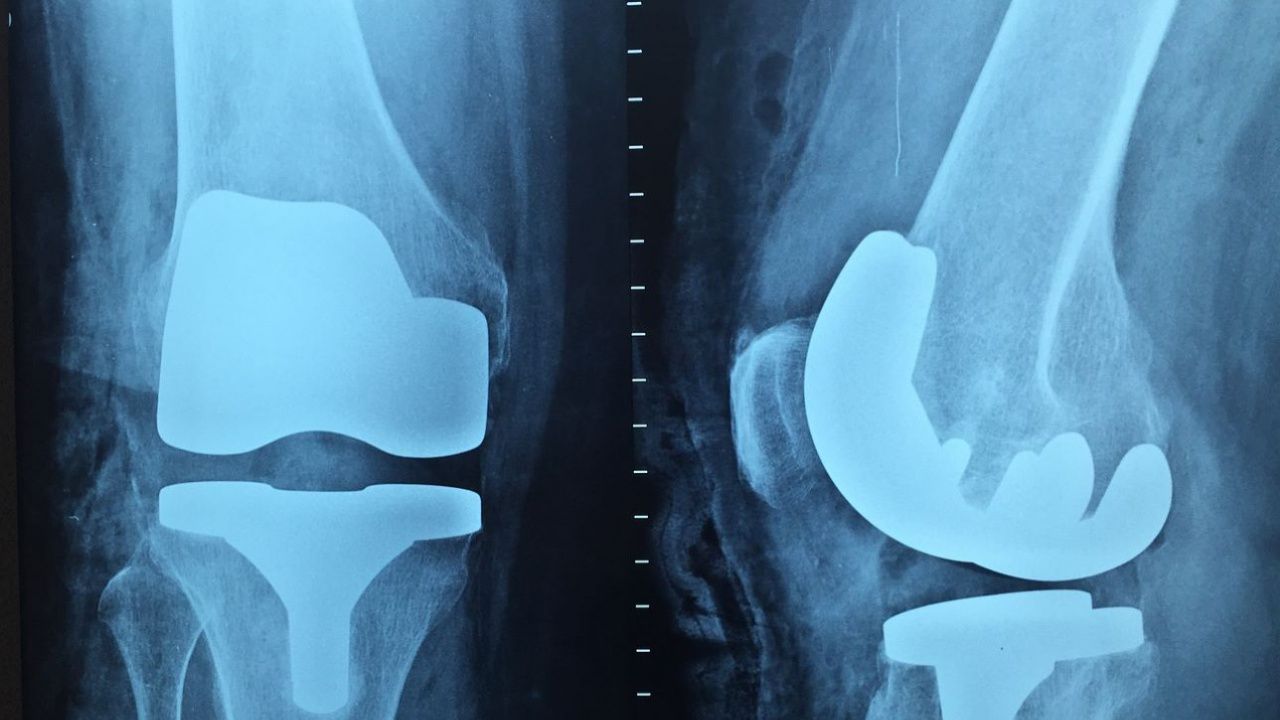

Основен акцент на събитието е практическа част, където ще се разглеждат различни техники за ендопротезиране.

Става дума за курсът по еднопротезиране AO Recon - Complex Total HipandKneeArthroplastyCourse. Той е част от програмата от събития на международно признатата Фондация АО, създадена да обучава ортопеди от цял свят в съвременните техники за лечение на фрактури. За четвърти път Клиниката по ортопедия и травматология на УМБАЛ „Царица Йоанна – ИСУЛ" ще бъде домакин на събитието.